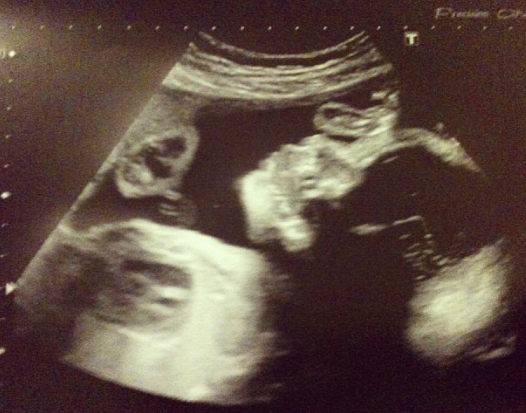

Anyway, at my consultant appointment yesterday my usual midwife did a general check over before I saw my consultant. One of the checks she did was the growth again, of course yet again that silly tape measure said my bump was small. Was told I wo

uld have to have another growth scan, wasn't expect to have it 10 minutes later. I guess the scan room is all set up in case the consultant wants any of the women she sees scanned. Of course again it confirmed that baby's growth was fine. The placenta and the fluid was all ok and the estimated fetal weight given was 1755.0g, I was given a EFW of 1114.0g when I had my first growth scan at 28 weeks. The Sonographer plotted the ones on the graph which are circled where as the ones which are little crosses are the midwives. Everything is perfectly ok with baby and he's all set up to be nice and healthy when he's delivered, though I wont be surprised if this wasn't my last growth scan in this pregnancy.